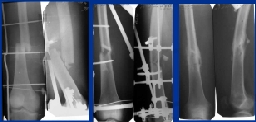

Рис. 6. Больной Г., 17 л., по поводу поперечного оскольчатого перелома диафиза бедра в средней трети выполнен остеосинтез спице-стержневым аппаратом. Фиксация в аппарате 75 сут. Рентгенограммы до операции (А), после остеосинтеза (B), через 6 мес. после травмы.

При большем смещении следует освободить кронштейн со стержнем, переместить на нужное расстояние и закрепить в другом отверстии опоры. В тех случаях, когда этим приемом достичь репозиции не удается, следует ввести еще один стержень вблизи перелома, перпендикулярно имеющемуся, то есть с передней поверхности бедра в сагиттальной плоскости, и смещать отломок дозированным перемещением этого стержня в кронштейне. В этом случае каждый стержень позволяет перемещать отломок непосредственно во фронтальной и сагиттальной плоскостях, в которой выполняются стандартные рентгенограммы, что облегчает расчет необходимой величины коррекции. Мы не рекомендуем вводить стержни в сагиттальной плоскости дистальнее середины диафиза бедра во избежание образования рубцов между прямой мышцей бедра и костью. При использовании описываемой технологии остеосинтеза такое введение на этом уровне практически никогда не является необходимым. Клинический пример применения описанной технологии представлен на Рис. 6.